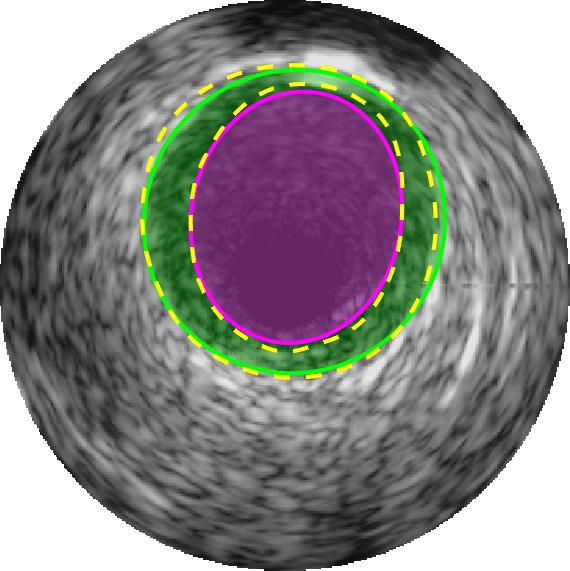

Qualitative evaluations are illustrated in Figure 4 and show the successful segmentation results of the proposed EREL selection strategy for 20 IVUS frames. The lumen areas are highlighted by the magenta colour while the media regions are green. Also, the manually annotated contours for both lumen and media are drawn as yellow dashed lines. As we can see, the chosen frames contain a variety of lumen and media morphologies.